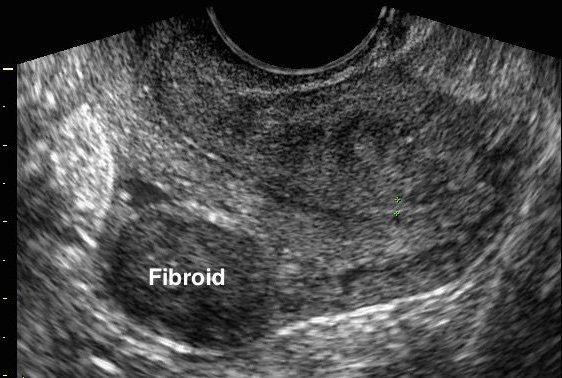

- Transvaginal Scan

- The scan provides detailed images which help to determine if the pelvic organs are normal or have abnormalities such as:

- Fibroids